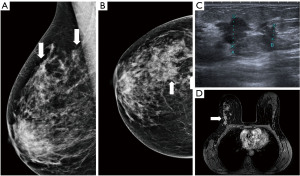

Figure 10 Mammography of the left breast in cranio-caudal view (A) with architectural distortion (arrow). The distortion is more visible in DBT (B) (arrow). Ultrasound (C) reveals subtle finding of irregular area of decreased echogenicity (arrow). MRI (D) shows extensive area of non-mass-like enhancement in the whole lateral part of the breast (arrow). DBT, digital breast tomosynthesis; MRI, magnetic resonance imaging. - Diagnostic assessment, a patient of 45 years of age with a palpable lump on the right side for 2 months. In mammography with higher proportion of fibroglandular tissue (category C) several areas of increased density with irregular margins and architectural distortions are visible. Ultrasound confirms more than one lesion. MRI demonstrates a large area of enhancement up to 7 cm (Figure 11).

Figure 11 Mammography of the right breast in medio-lateral-oblique (A) and cranio-caudal view (B) with multiple densities with irregular margins and architectural distortions (arrows). Ultrasound (C) shows more than two hypoechoic lesions of suspicious features. In MRI (D) an extensive area of tumour involvement is revealed. MRI, magnetic resonance imaging. - A patient of 50 years of age evaluated for enlarged lymph nodes in the axilla. Mammography and ultrasound show enlarged pathological lymph nodes in the axilla, otherwise no pathological finding in the breast on initial evaluation despite the low mammographic density. The largest lymph node is biopsied proving metastatic invasive carcinoma NST of breast origin. MRI is indicated to search for an occult lesion in the breast. MRI shows the enlarged lymph nodes and a small lesion in the right breast in upper outer quadrant. A second-look, targeted ultrasound with the knowledge of the location of the lesion is performed to reveal a small suspicious lesion, which is subsequently verified as the primary tumour in the breast (Figure 12).